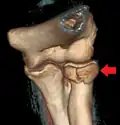

| Radial head fracture (red arrow) with posterior and anterior sail sign (blue arrows) | |

CT scan showing a radial head fracture -

Radial head fracture seen on 3D CT reconstruction